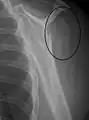

Proximal

Proximal humerus fractures most often occur among elderly people with osteoporosis who fall on an outstretched arm.[9] Less frequently, proximal fractures occur from motor vehicle accidents, gunshots, and violent muscle contractions from an electric shock or seizure.[10][5] Other risk factors for proximal fractures include having a low bone mineral density, having impaired vision and balance, and tobacco smoking.[11] A stress fracture of the proximal and shaft regions can occur after an excessive amount of throwing, such as pitching in baseball.[6]